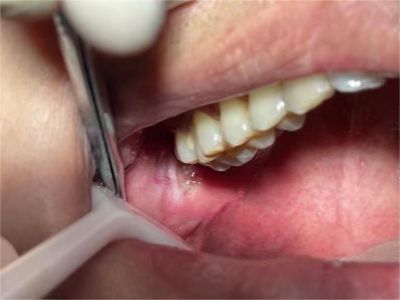

唇内侧

溃疡

创伤性溃疡口腔黏膜上有一块红溃疡图

创伤性溃疡是因长期刺激所引发,唇内侧黏膜发红,靠近牙齿部位有数个白色小溃疡,持续刺激后创面会出现炎性增生,若未继发感染,解除刺激后可较快愈合。